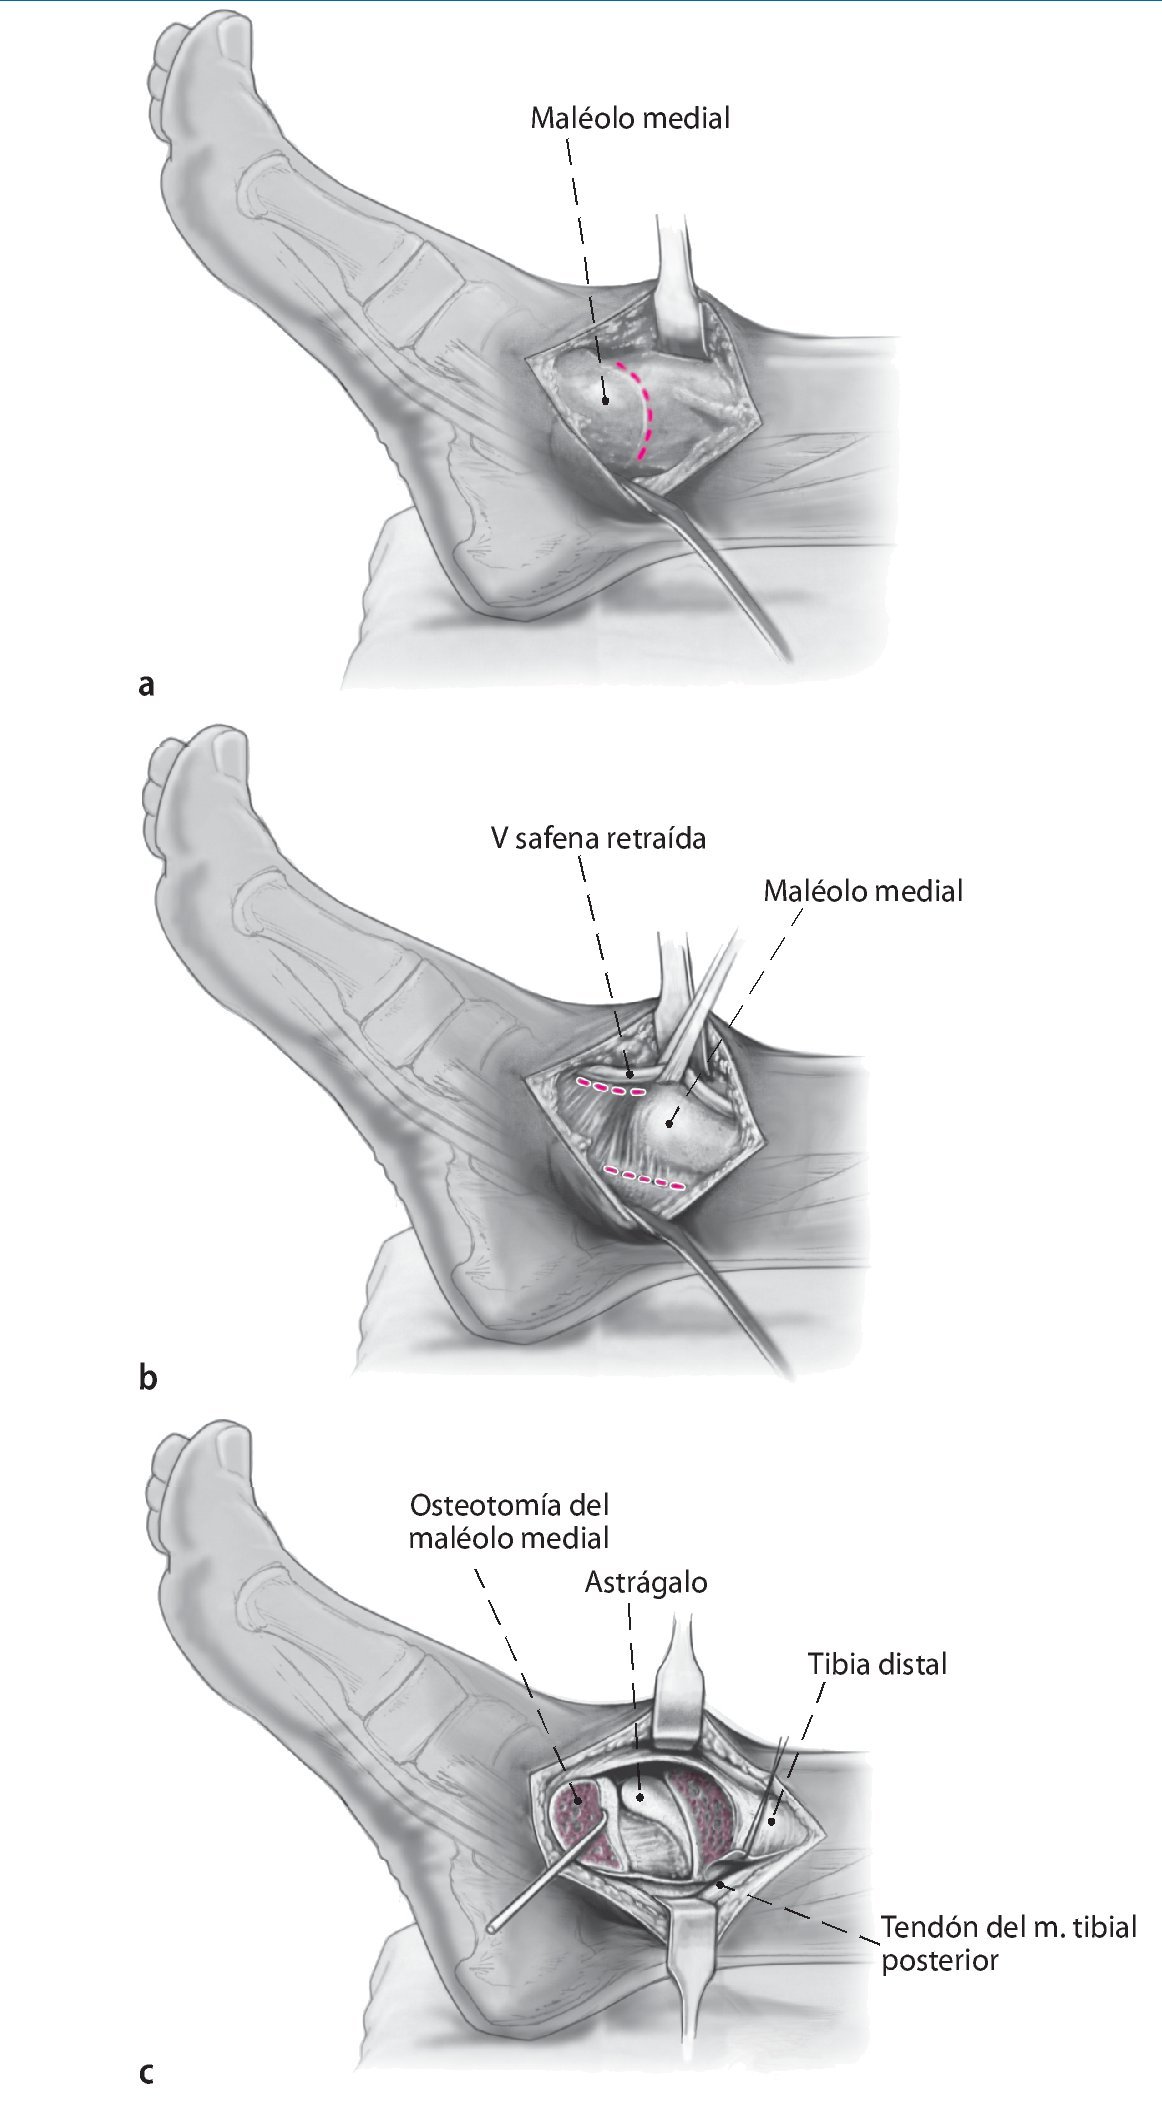

Fig. 2 La incisión medial se lleva a cabo hasta el periostio (a). El daño a la vena safena mayor se evita mediante su retracción anterior. En el lado anteromedial, se reseca parcialmente la cápsula anterior (b). El retináculo extensor y los tejidos blandos se pueden mover como una capa para exponer la sección anteromedial de la articulación del tobillo. Se realiza incisión posterior del retináculo sobre el tendón tibial posterior para permitir la colocación protectora de un separador de Hohmann (b). La osteotomía del maléolo medial se realiza con sierra oscilante y se reseca la porción distal (c).